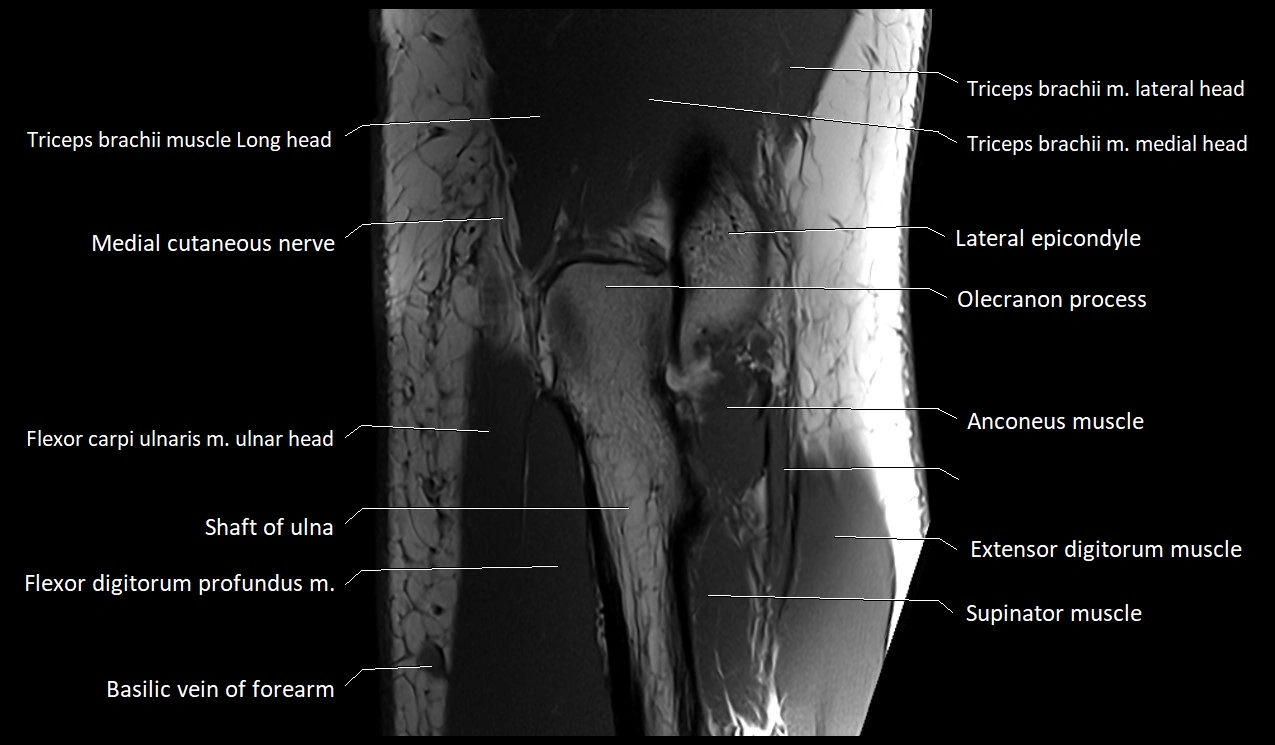

MRI image

image